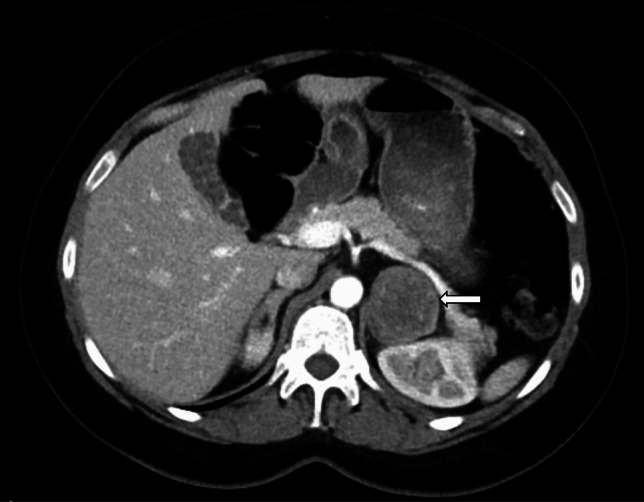

Abstract Image